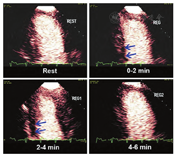

自2008年ASE共识声明发表以来,许多相关研究报道了RTMCE在灌注成像评估中的可行性、安全性、诊断和预后准确性,特别是在血管扩张剂负荷超声心动图,加强了血管扩张剂负荷方式与RTMCE结合使用的证据[27,39,41,43,47,48,50,51,52,53,55,56,64]。与正性肌力负荷相比,血管扩张剂负荷灌注成像可提供同等的检测CAD的信息,而且具有操作迅速和由于心率较低(通常不超过100次/min)而可能具有更好图像质量和较少心脏平移运动的优点(图7)。

然而,常规检测负荷诱发的RWM异常在某些情况下可能不太敏感,因为这种负荷模式不依赖于心肌需氧量。几种血管扩张剂已用于RTMCE的研究,即腺苷[16,43,47,50,51]、潘生丁[26,27,41,43,48,52,53,55]以及最近的瑞加德松(regadenoson)[54,64]。腺苷和潘生丁是灌注成像中最常用的血管扩张剂,两种药物都非选择性的直接或间接地活化所有四种腺苷受体亚型(A1,A2A,A2B和A3),这可能导致胸痛、轻度呼吸困难、低血压、支气管痉挛以及少见的可逆性房室结阻滞。瑞加德松是一种有效的选择性A2A激动剂,以400 μg静脉推注给药,具有快速起效(30 s内)和足够的作用持续时间以允许足够的时间进行图像采集(达4 min),并且副作用较小,它可能会成为灌注成像的首选血管扩张剂之一(图8)。来自灌注数据的信息对于所有这些血管扩张剂是等同的,因此可以根据当地的药物可用性、成本、副作用和感知的实际优点或缺点来定制每种血管扩张剂的选择。

视觉定性分析更容易学习和减少劳动强度(图7和图8,视频10;可从www.onlinejase.com获得)。以下经验法则可用于结果判读:使用2D超声探头进行静息再充填应该在高机械指数脉冲闪击破坏后5 s内,在负荷状态下应2 s内再充填(视频6和7;在www.onlinejase.com获取)[1]。